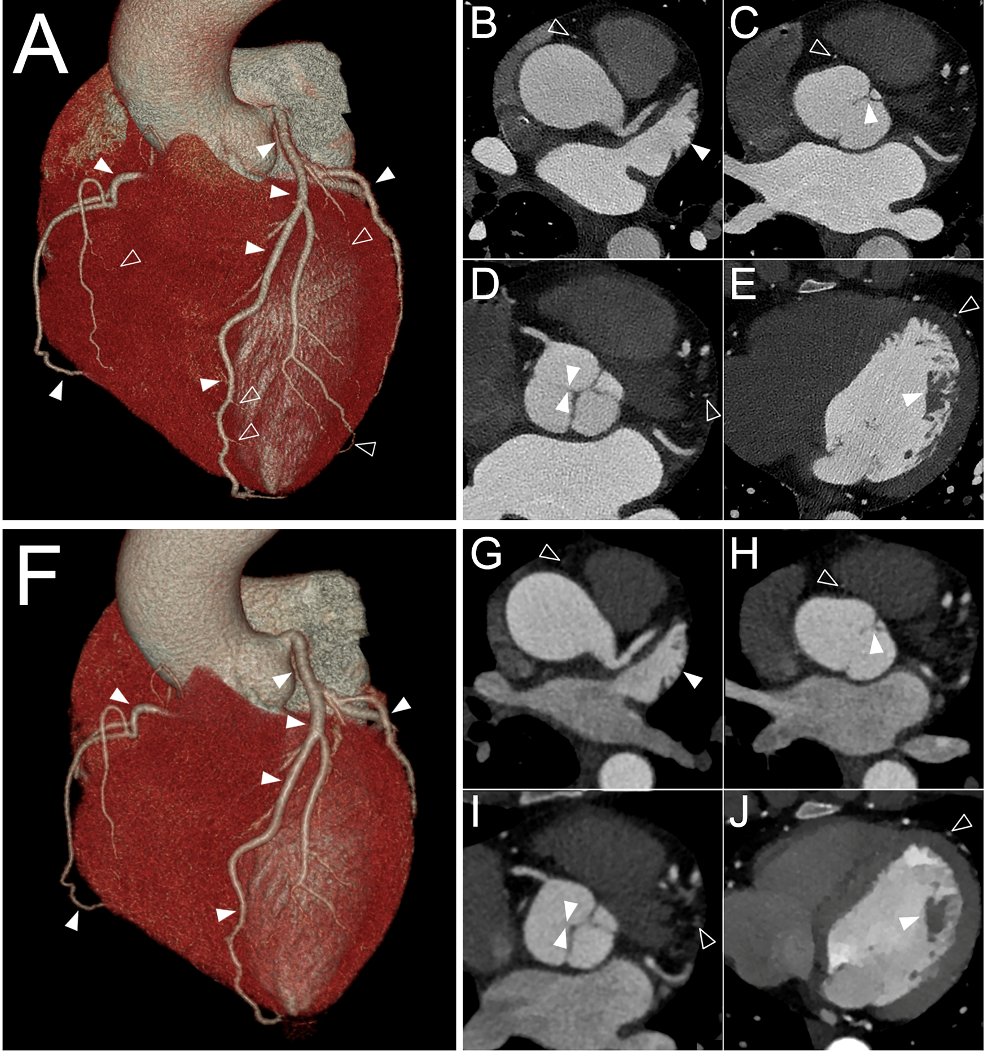

Time to consider a reduced-iodine-dose dual-energy CT angiography for your patients👍 philippe douek @david_rotzinger Mickaël OHANA Reduced-iodine-dose dual-energy coronary CT angiography: qualitative and quantitative comparison between virtual mo… pubmed.ncbi.nlm.nih.gov/33740093/

💡Imagerie médicale : du noir et blanc à la couleur ! Le Scanner Spectral à Comptage Photonique repousse les limites du scanner standard dans l'évaluation des pathologies cardiovasculaires et neuro-vasculaires ➡️bit.ly/3JzkGZW #technologie #innovation #santé #presse

💡Imagerie médicale : du noir et blanc à la couleur ! Le Scanner Spectral à Comptage Photonique repousse les limites du scanner standard dans l'évaluation des pathologies cardiovasculaires et neuro-vasculaires ➡️bit.ly/3JzkGZW